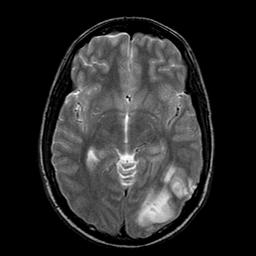

Sarcoma, MR Study #1 mr-t2 -- Slice #10

[Home][Help][Clinical] Slice 10